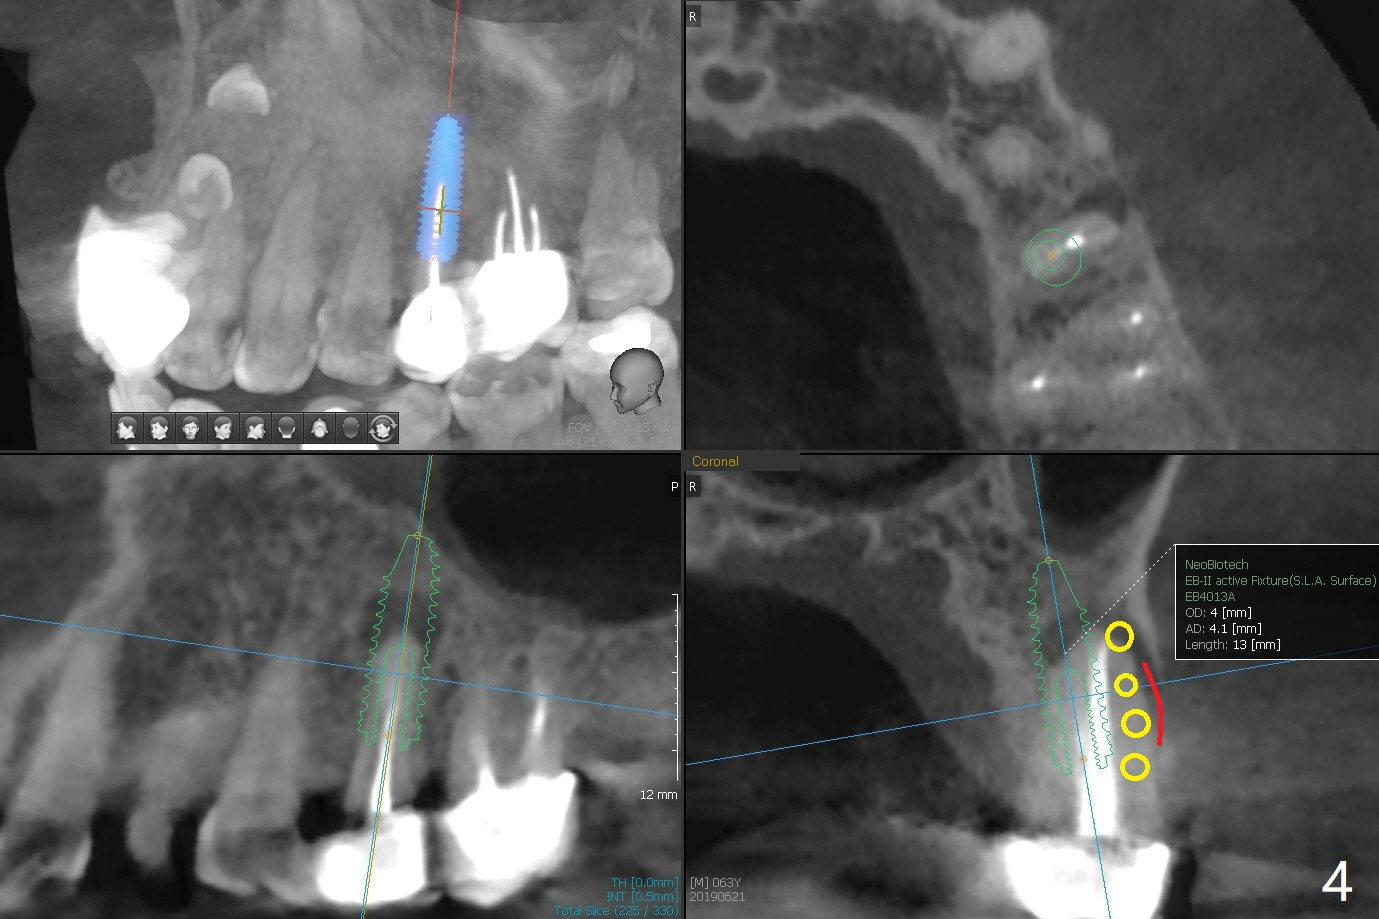

46岁男有多个修复物,左上第二前磨牙时常肿痛(13号牙),根尖阴影大(图一(CT一年前)箭头),根尖颊侧似乎折裂(图二箭头),颊侧牙槽嵴骨质仿佛存在(图三B),即刻种植可行(图四绿色),使用PRF膜(红色)和粘性骨块(黄色)同期修复颊侧骨板缺损。